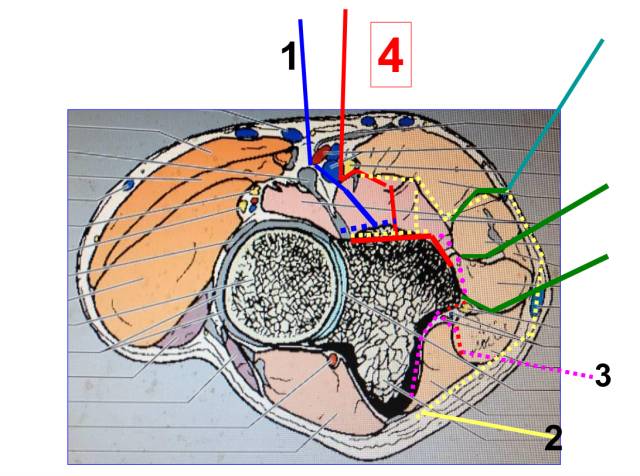

肘窝的构成

• 内侧旋前圆肌,外侧肱桡肌

• 内容:桡神经、前臂外侧皮神经、肱二头肌腱、肱动脉、正中神经、肱肌